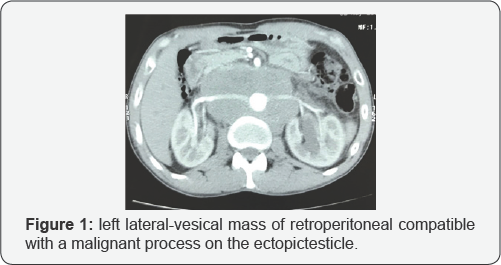

Abdominal ultra sound showed a mass of the left iliac fossa with left uretero-hydro nephrosis. The thoraco-abdomino-pelvic CT scan (Figure 1) demonstrated a left lateral-vesical mass of retro peritoneal extension tissue compatible with a malignan process on the ectopic testicle with a retro peritoneal abdominal lymph adomectomyencom passing large vessels and A left uretero-hydronephrosis (Figure 2). Surgical exploration revealed a voluminous left ateral-vesical poly lobal testicular tumor. The anatomo pathological examination concluded in a seminome on ectopic testicle with invasion of the epididymis and infiltration of the albuginea without lympho-vascular invasion. The patient received just after 3 BEP cures (bleomycin, etoposide, cisplatin). The thoraco-abdomino-pelvic CT scan and tumor control markers were not shown to have residual mass.